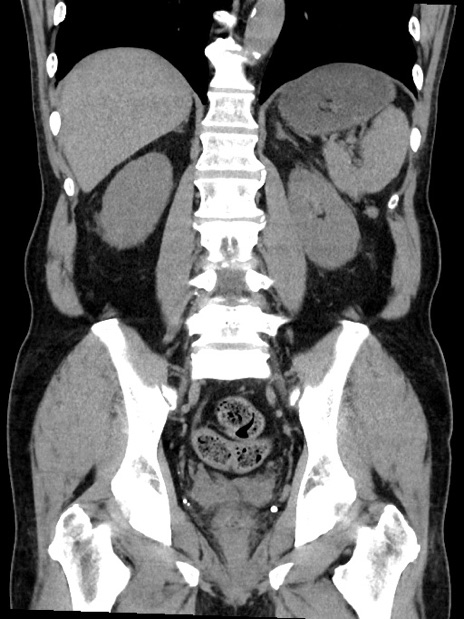

症例35(冠状断像)

【症例】70歳代 男性

【主訴】腹部膨満、嘔吐

【現病歴】昨日より腹部膨満感出現。本日増悪し、仙痛出現。嘔吐あり、受診。

【既往歴】糖尿病、胆摘後

【身体所見】BP 149/80mmHg、HR 74/min、BT 35.9℃、腹部:膨満、軟、圧痛なし。腸雑音減弱あり。上腹部正中切開瘢痕あり。

【データ】WBC 13500、CRP 1.72